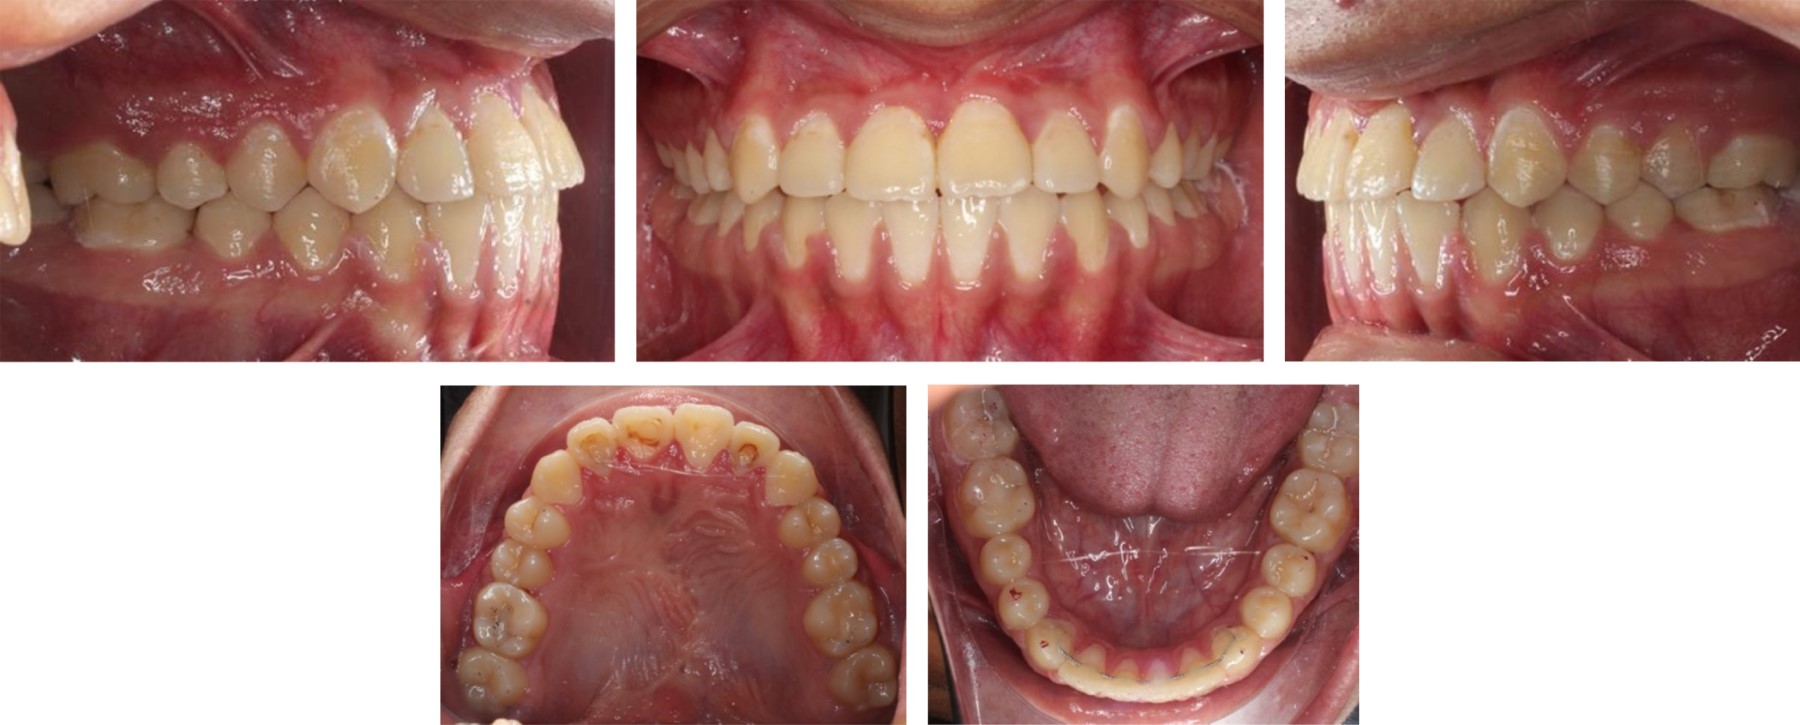

The duration of treatment was 48 months, the position of dental organs #11 and #21 was adequate, the overbite was corrected, bilateral class I canine and class I molar were achieved, a positive arch smile, correct anterior guidance (overjet and overbite), coincidence of midlines, elimination of open bite in the anterior sector (Figures 5 and 6); the correct position of the dental organs #11 and #21 was observed in the radiographic examination, with no root resorption and, bone neoformation adjacent to the traction site (Figure 7).

• Figure 1

Figure 2